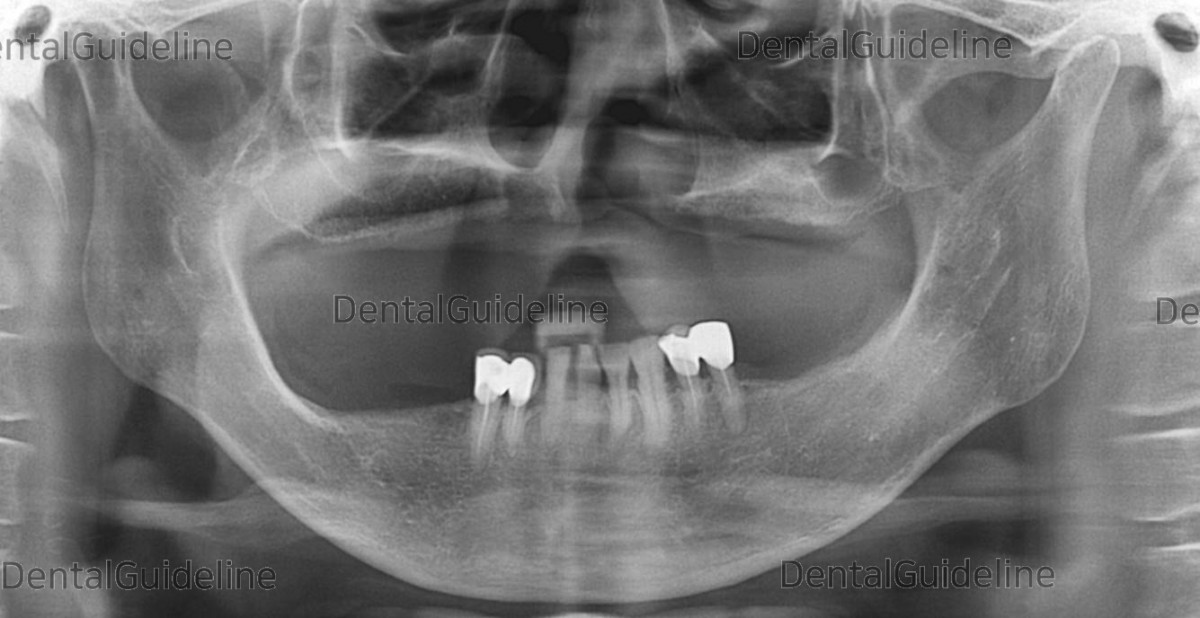

Pt. was wearing dentures (Mx-full denture, Md-partial denture). Pre-op panoramic radiograph.![]()

A panoramic radiograph after implant surgery.![]()